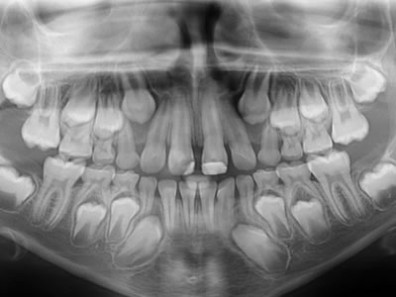

Na técnica de Clark se realiza uma sequência de três radiografias com angulações diferentes (orto, meso e disto radial) a fim de se localizar estruturas em relação às adjacentes. Como o objeto mais distante parecerá mover-se na direção da fonte de radiação, o objeto mais próximo parecerá mover-se na direção oposta.